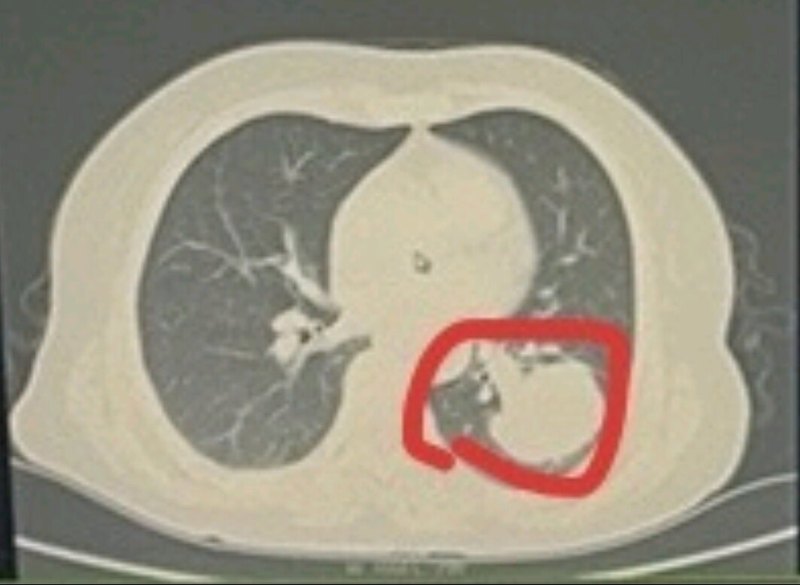

乳腺癌腦轉(zhuǎn)移介紹大家好,今天聊一聊乳腺癌腦轉(zhuǎn)移的一些情況。我們當乳腺癌細胞并不局限于乳房,而是通過血液等循環(huán)進入腦組織內(nèi),出現(xiàn)浸潤和侵犯,那最終就會形成腦轉(zhuǎn)移病灶。請大家看圖中所示的內(nèi)容,我們圖片中間啊,大腦中央有一個像乒乓球大小的東西,那就是我們的一個腦轉(zhuǎn)移瘤,如果患者近往得過乳腺癌,有可能是乳腺癌轉(zhuǎn)移。腦轉(zhuǎn)移瘤是我們腦瘤里面非常常見的類型,它的發(fā)病率甚至高于我們原發(fā)的腦腫瘤。我們所有的惡性腫瘤患者大約20%-40%最終會出現(xiàn)腦轉(zhuǎn)移,其中乳腺癌是第二大的一個原發(fā)的啊,腫瘤的來源僅僅次于肺癌。在女性中,乳腺癌是最常見的惡性腫瘤。因此,腦轉(zhuǎn)移瘤是啊女性中啊最常見來源就是我們的乳腺癌。據(jù)不完全統(tǒng)計,乳腺癌腦轉(zhuǎn)移的發(fā)生率占所有乳腺癌患者的1/10。